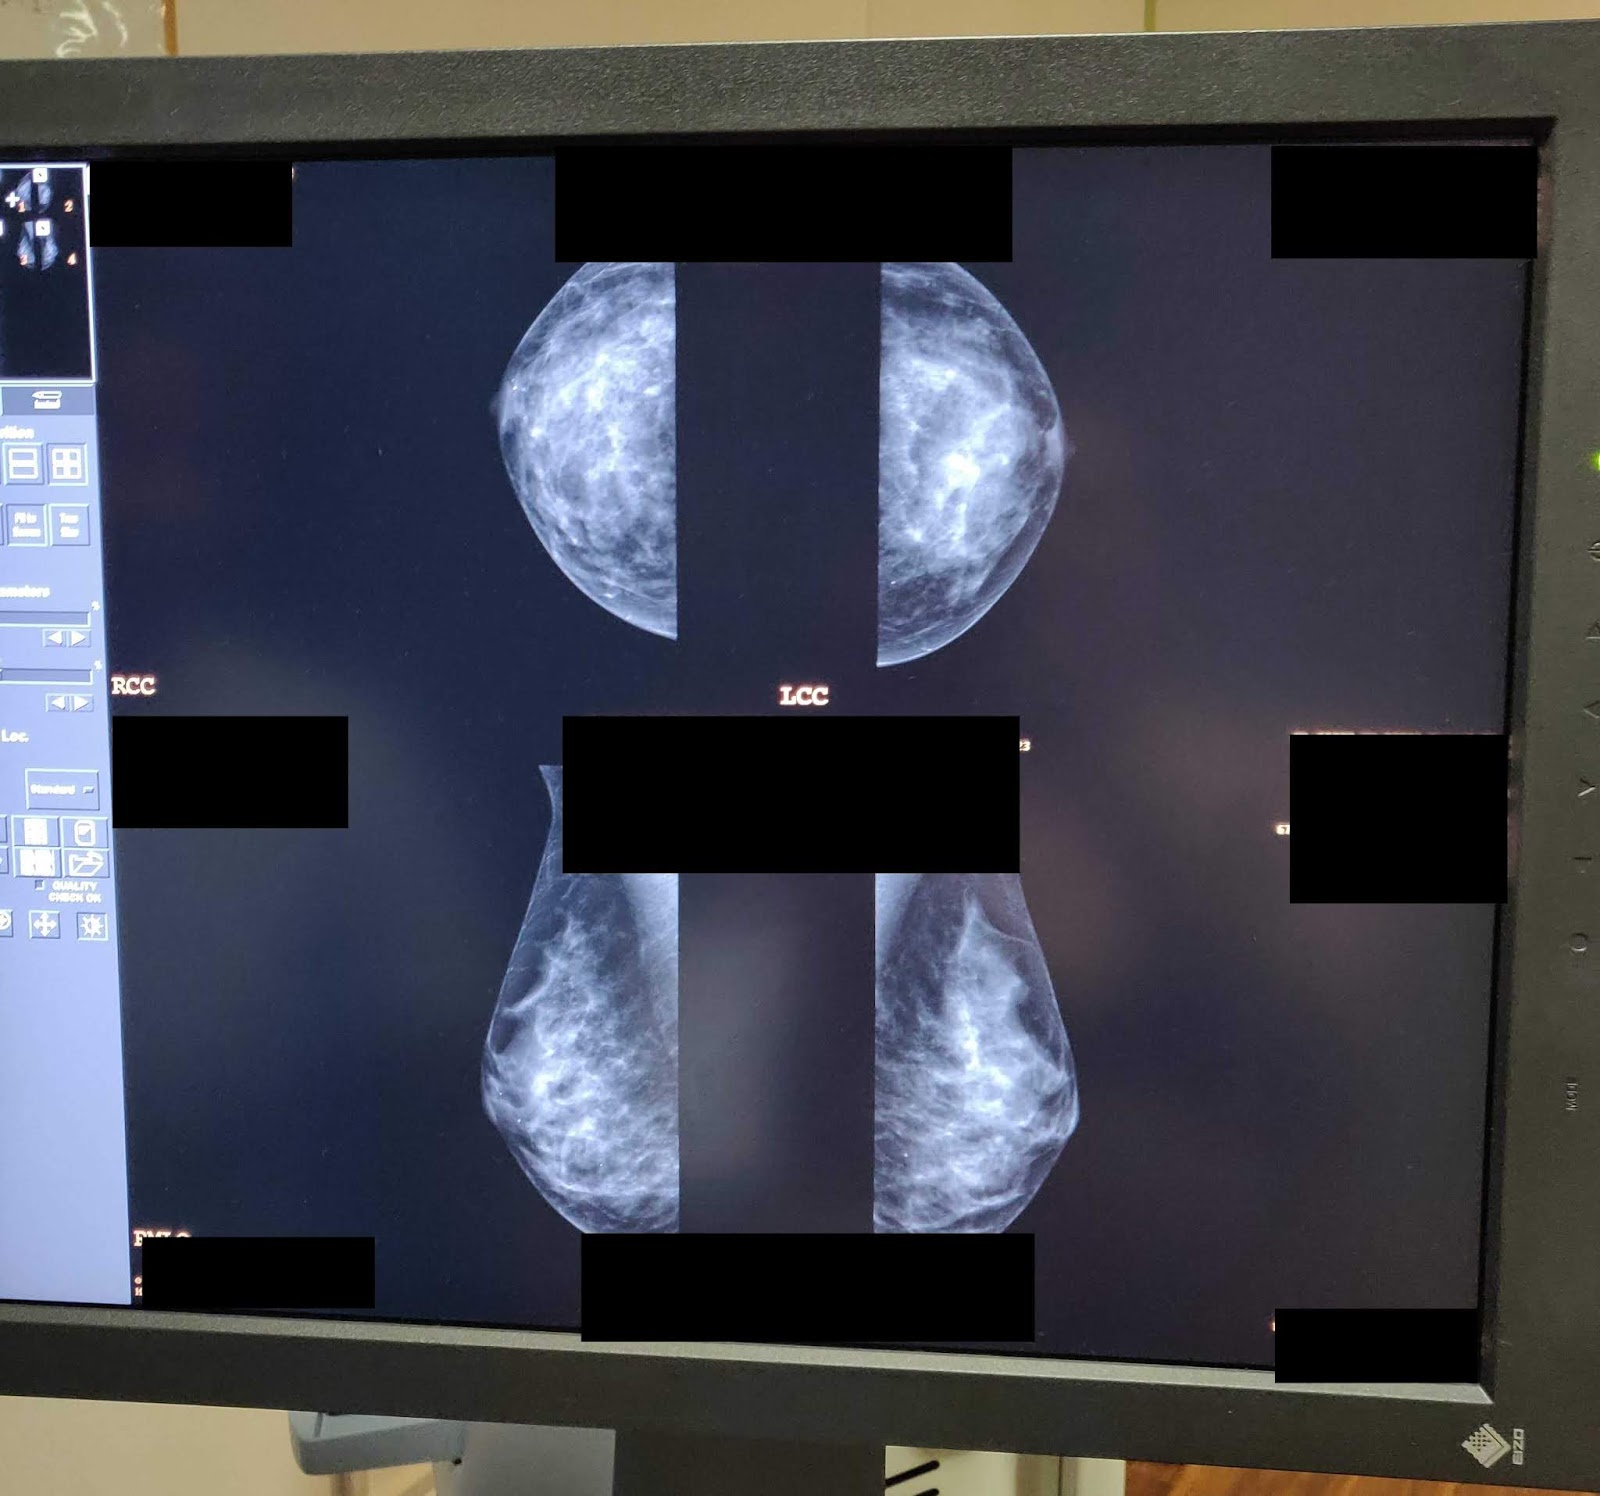

| The only picture of my boobs on the internet to date. |

My mom told me that she has dense breast tissue and needs to have an ultrasound after her mamogram as part of her annual appointment. I was worried this would be the case for me but the nurse who performed my mamogram didn’t think this would be the case based on my images. My friend who’s mom had breast cancer informed me that in the US, patients are often called back for another mamogram after their initial one as there is no baseline to compare the x-ray to. I haven’t heard of this happening in the UK though.